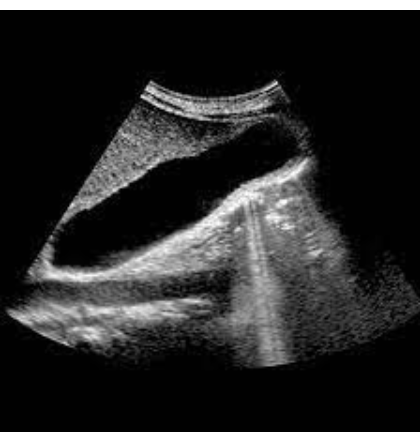

What Pathology is in the image below

Distention/Hydrops - enlarged gallblader intravenous